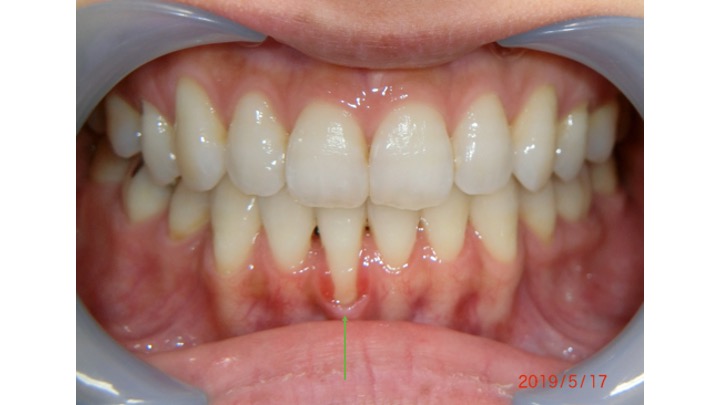

• 見た目の改善: 歯肉が下がることで、笑った時に歯が長く見えることがあります。根面被覆術により、自然な歯ぐきのラインを取り戻すことができ、見た目も向上します。